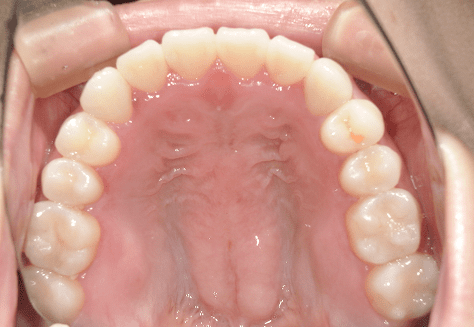

M.H

治療前

治療後

主訴

前歯が出ている。下の歯並びが特に気になる。奥歯でしっかり噛めない。

診断

上顎前突・叢生・シザーズバイト

年齢/性別

20代/男性

抜歯部位

下顎両側大三大臼歯(口腔外科にて)

上顎両側第一小臼歯・下顎左側側切歯

(当院にて5,500円×3) -

使用装置

上下エッジワイズ→インビザライン(PBM使用)

保定装置

上下ビベラリテーナー

料金

初回資料採得・・・・・・・30,000円

診断料・・・・・・・・・・33,000円

動的治療終了時資料採得・・5,500円 -

基本料金

880,000円

診察料金

5,500円×44回

-

治療期間

3年6カ月